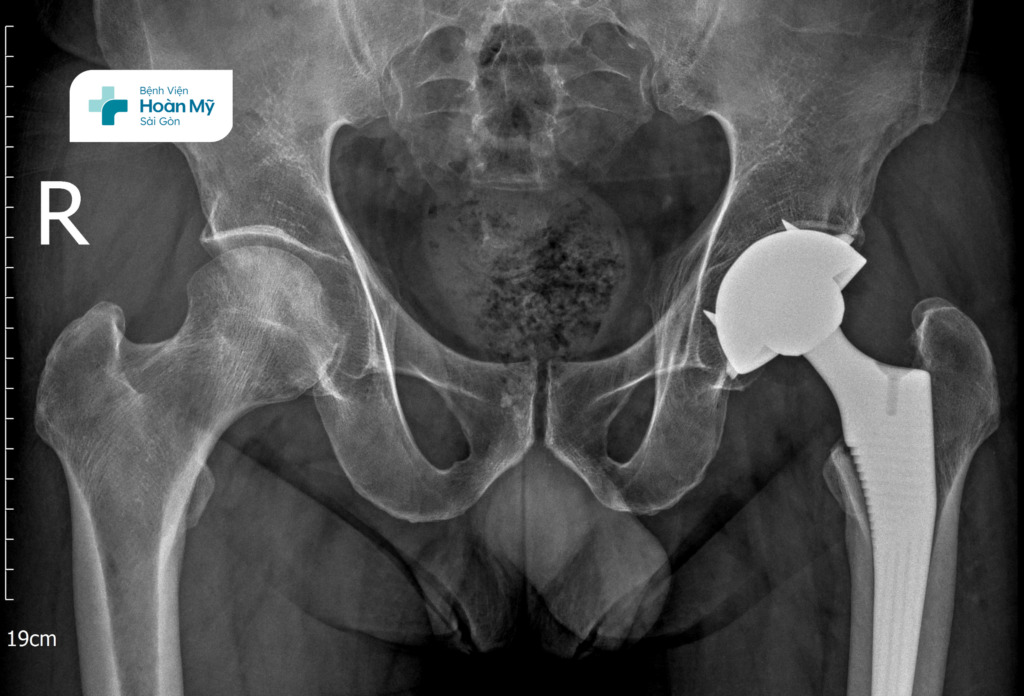

Sau một thời gian không cải thiện và khi tình trạng đi lại hạn chế nhiều, người bệnh quyết định đến Bệnh viện Hoàn Mỹ Sài Gòn để được can thiệp chuyên sâu. Tại đây, anh P. được khám và chẩn đoán bệnh: hoại tử chỏm xương đùi hai bên (bên trái tổn thương nặng hơn).

Sau khi thăm khám và đánh giá hình ảnh cận lâm sàng như XQ, MRI, BS.CKII. Hồ Trương Đăng Triều, khoa Chấn thương chỉnh hình, Bệnh viện Hoàn Mỹ Sài Gòn nhận định: Tình trạng khớp háng bên trái của người bệnh đã tiến triển đến giai đoạn nặng không còn khả năng giữ lại, ảnh hưởng nghiêm trọng đến cấu trúc và chức năng của khớp. Việc thay khớp háng toàn phần được chỉ định nhằm phục hồi

lại hình dạng của khớp, giảm đau hiệu quả và giúp người bệnh sớm quay trở lại lao động sinh hoạt như bình thường.

Trong khi đó, khớp háng phải vẫn còn khả năng bảo tồn (không thay khớp), phù hợp với phương pháp phẫu thuật giảm áp cổ xương đùi. Mục đích của phương pháp này là làm giảm áp lực bên trong xương, cải thiện tuần hoàn vùng chỏm và làm chậm quá trình hư khớp.

Hình ảnh phim X-quang người bệnh sau khi thay khớp háng